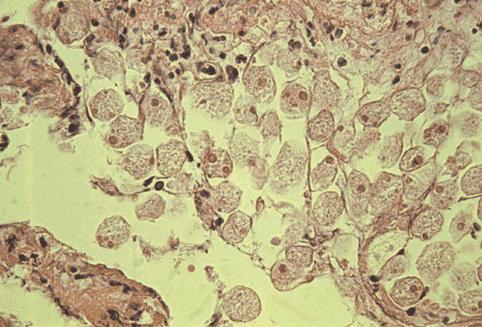

아메바 적리

회맹부와 직장~S상결장에 병변을 나타낸 대장 아메바성 대장염

염증성 및 궤양성질환/아메바성 대장염

대장/맹장

마이크로